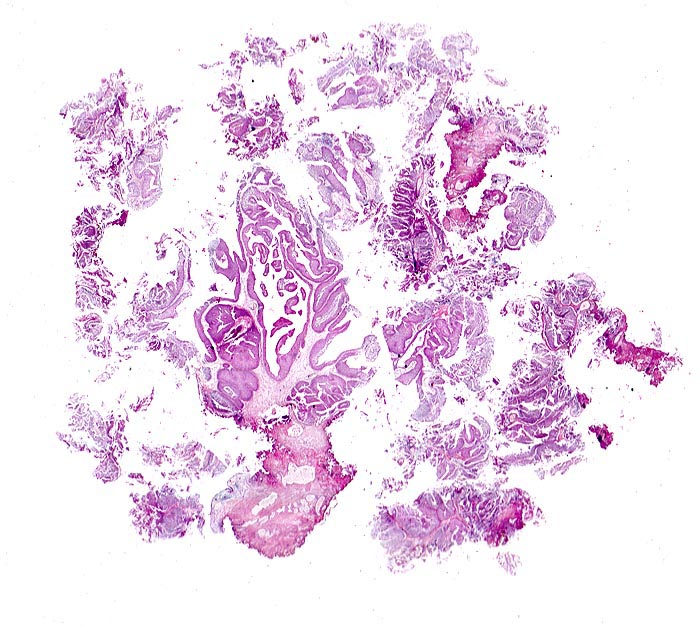

• Transurethrale Resektate von Harnblasenschleimhaut mit papillärem Tumor.

• Entnahmebedingte Kauterartefakte (dünn ausgezogene Zellen und Chromatinschlieren, ausgefranste Abtragungsränder).

• Das neoplastische Urothel bildet fingerförmige, teils miteinander verschmelzende Papillen mit schmalen fibrovaskulären Stromastielen.

• Das neoplastische Urothel ist verbreitert (meist mehr als 7 Zellagen).

• Scharfe Grenze zwischen Epithel und subepithelialem Stroma (keine Invasion).

• Mässiggradige Dysplasie des neoplastischen Urothels (G2, low grade): Tumorzellen mit vergrösserten, leicht pleomorphen Zellkernen. Zahlreiche Apoptosen. Herdförmiger Polaritätsverlust (fehlende Ausrichtung der Zellen in der Längsachse).

• Auf diesem Schnittpräparat sind kein tumorfernes Urothel und keine Anteile der Harnblasenwandmuskulatur enthalten.